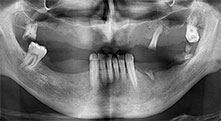

Le Professeur Emanuel Bratu, chirurgien maxillo-facial, stomatologue et prothésiste, dirige les départements d'implantologie dans deux universités roumaines. Il dirige un hôpital privé renommé à Timisoara et c'est un chercheur internationalement connu. Dans cet entretien, le Dr Bratu explique pourquoi il pense que l’unit de chirurgie piézoélectrique Piezomed de W&H, et en particulier deux scies brevetées, sont devenus essentiels en chirurgie osseuse.

Professeur Bratu, quelle est votre expérience des nouvelles scies B6/B7 pour le Piezomed de W&H ?

Pr Bratu : Ces scies sont radicalement différentes des instruments de chirurgie piézoélectrique connus jusqu'à présent. Elles sont d'une efficacité étonnante. Nous avons immédiatement remarqué que les B6/B7du Piezomed sont beaucoup plus rapides que les autres scies. Elles sont également plus faciles à guider dans l'os, en particulier dans les couches osseuses épaisses.

D'après W&H, cela s'explique par la puissance élevée de l'unit de chirurgie, ainsi que par les dents très fines et le diamètre réduit des lames de scie, qui ne dépasse pas 0,25 mm.

Pr Bratu : Nous utilisons couramment les instruments pour le prélèvement des blocs osseux et le clivage de la crête alvéolaire. Nous utilisons également les scies B6/B7 Piezomed pour l'ostéotomie des dents endommagées et l'extraction des implants défaillants. Bref, toutes les indications qui nécessitent des coupes profondes et propres.